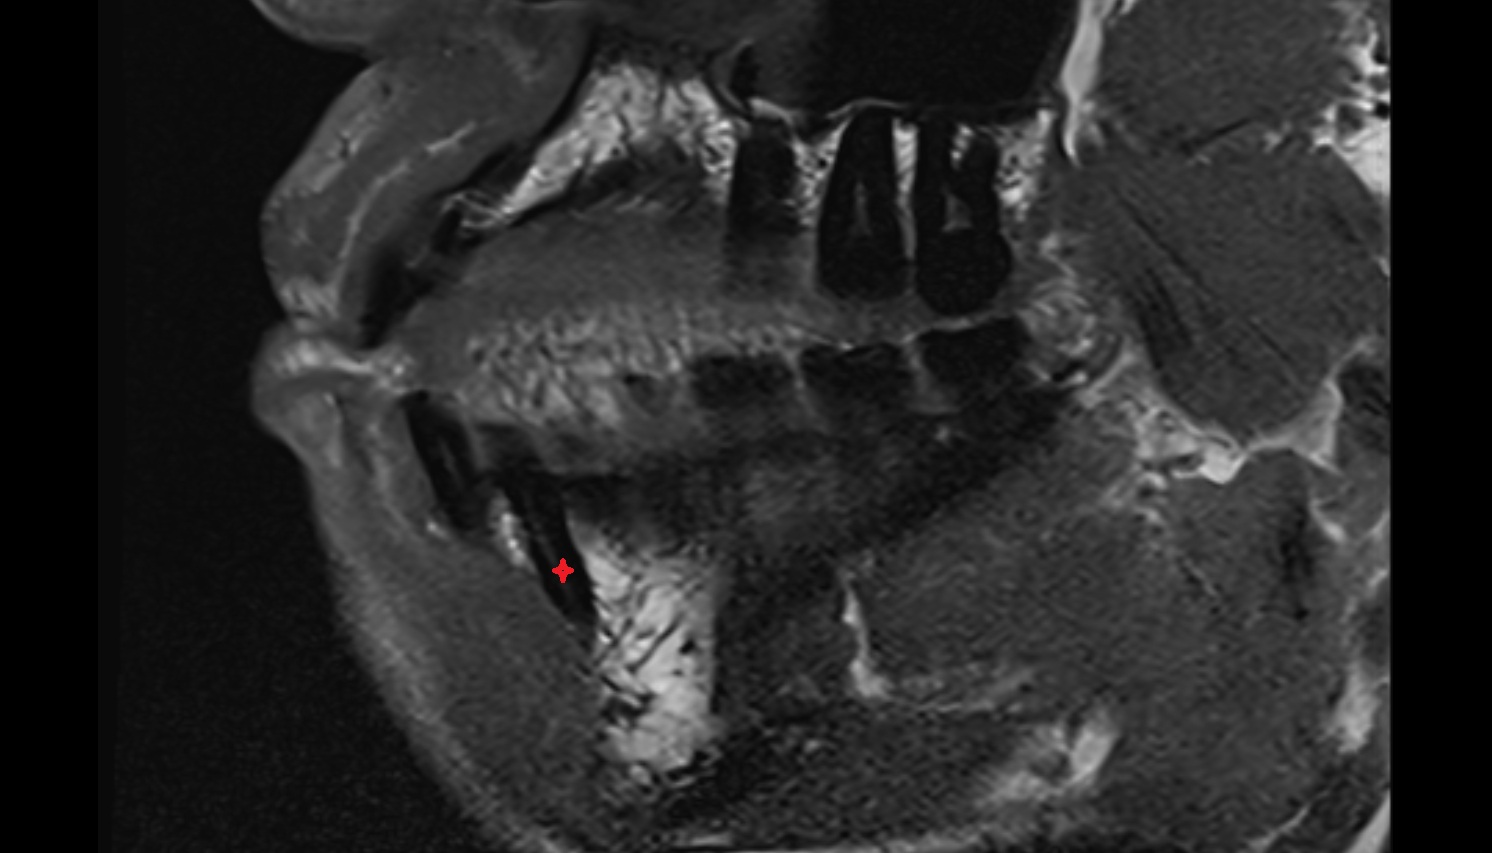

- Temporomandibular joint

- Articular disc of temporomandibular joint

- Articular eminence

- Mandibular condyle

- Mandibular fossa

- Superior head of lateral pterygoid muscle

- Inferior head of lateral pterygoid muscle